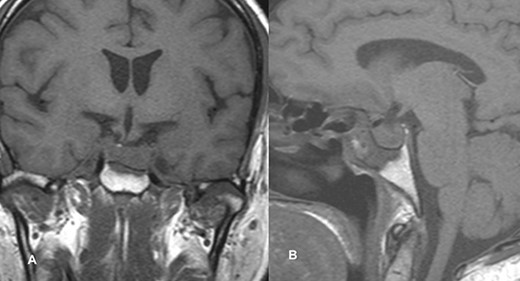

The patient underwent transsphenoidal pituitary adenectomy 3 days after admission. Intraoperatively, soft tumors with hemorrhagic components were seen. Hemostasis was achieved and the sella was packed with fat. The patient was managed in the ICU for 2 days and discharged on the 8th postoperative day. The ptosis gradually improved within 2 days of surgery, and during the 2-week follow-up in the outpatient clinic, the ptosis recovered completely. Follow-up imaging showed no evidence of a residual lesion in sella turcica (Fig. 4).

Follow-up imaging of case 2 showed no evidence of a residual lesion in sella turcica.